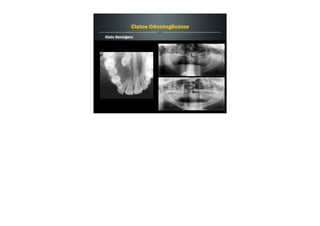

Características Radiográficas dos Cistos Odontogênicos

Radiograficamente os cistos apresentam-se como áreas

radiolúcidas, uniloculares, com margens bem definidas e

escleróticas.

Crescimento lento.

Indolor.

Provoca expansão das corticais ósseas.

Geralmente deslocam as estruturas adjacentes.

Podem induzir a reabsorção radicular.

O tratamento dos cistos odont. é a enucleação da lesão.